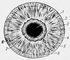

Внешний вид радужной оболочки глаза человека: 1 — зрачок; 2 — пигментный ободок; 3 — зрачковый пояс; 4 — малый круг радужной оболочки; 5 — контракционные бороздки; 6 — трабекулы; 7 — крипты; 8 — цилиарный пояс.